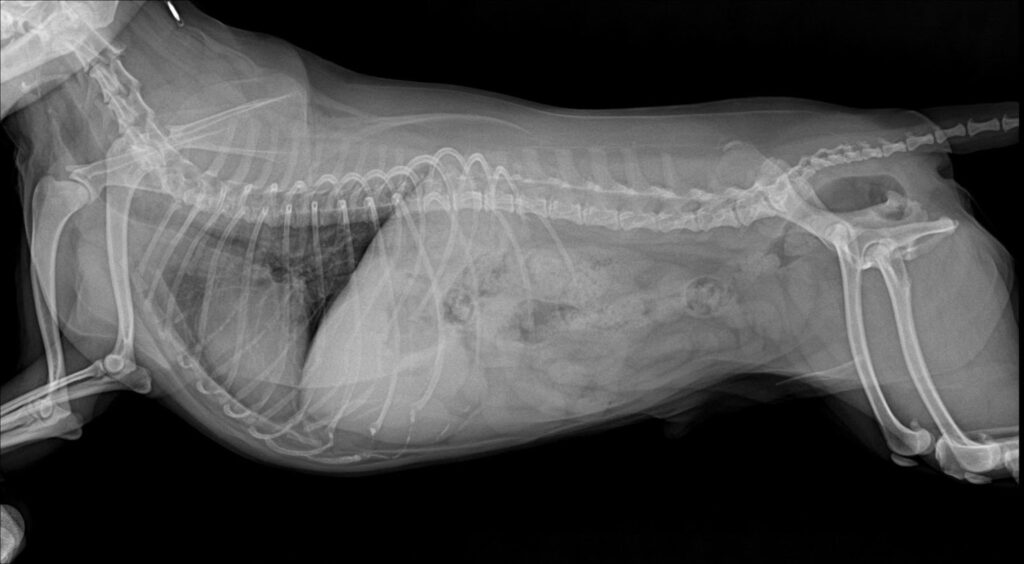

슬개골 촉진 검사에서 양측 슬개골 모두 내측 탈구가 확인되었고, 우측은 2–3기, 좌측은 4기로 진단되었습니다. 엑스레이 검사에서도 무릎뼈가 대퇴골 고랑을 벗어나 내측에 위치한 모습이 명확히 관찰되었습니다.

환자는좌측 슬개골 탈구의 진행 정도가 매우 심한 상태였기 때문에 보호자 상담 후 좌측 슬개골 탈구 수술을 진행하기로 결정했습니다. 수술 전에는 마취 전 혈액검사와 흉부 방사선 검사 실시하였습니다.

수술 전 방사선사진 / 출처: 미래동물의료센터